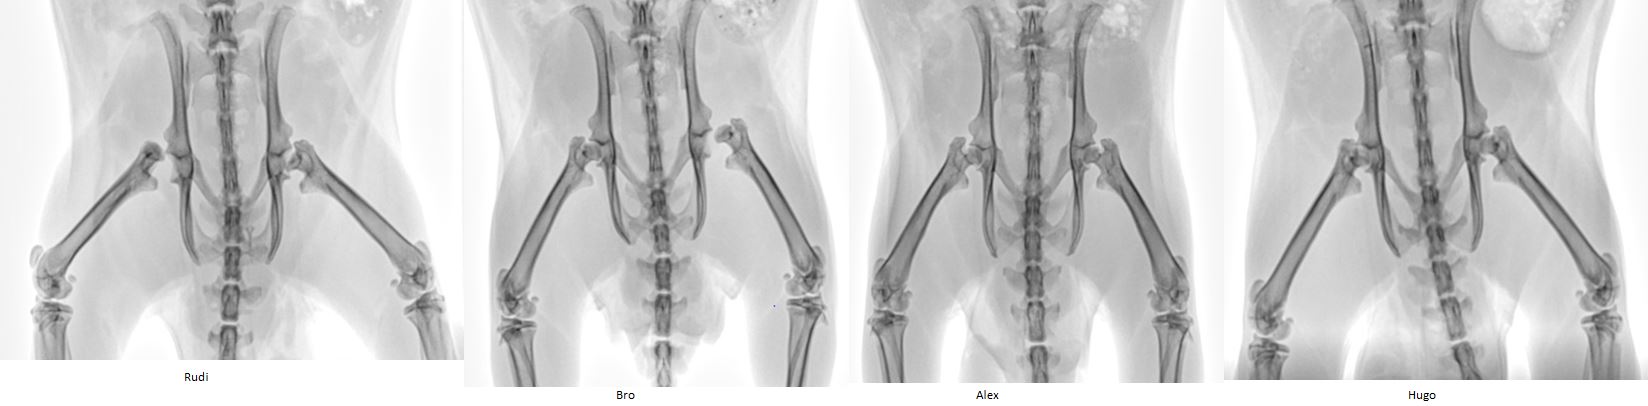

Rudi, Bro, Alex und Hugo kommen aus einem Versuchslabor im Alter mit ca. 6 Monaten.

Alle 4 Ratten wurden geröntgt, da schon Erfahrung von Hüftproblemen von Laborratten vorhanden waren.

Röntgenbild, alle 4 Labories